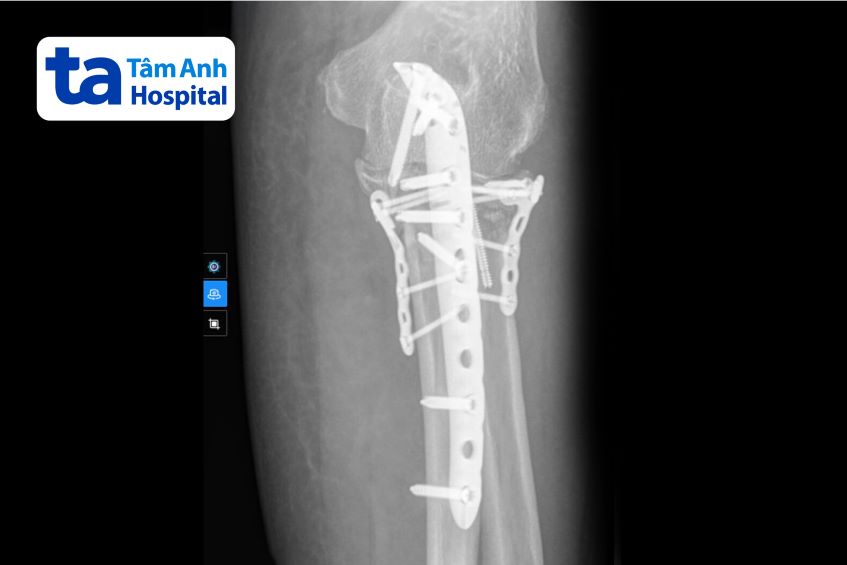

Kết quả chụp X-quang và CT tại Bệnh viện Đa khoa Tâm Anh cho thấy bà Lợi gãy rất phức tạp đầu trên xương quay và xương trụ tay trái. Phẫu thuật là phương pháp duy nhất giúp người bệnh hết đau và khôi phục vận động.

Để đảm bảo an toàn cho ca mổ, bác sĩ hội chẩn đa chuyên khoa, chỉ định Bà Lợi điều trị nội khoa trong 5 ngày, ổn định các chỉ số, đặc biệt là đường huyết. Trong phẫu thuật, bác sĩ tiếp cận ổ gãy chỉ bằng một đường mổ duy nhất, tiếp cận từ phía sau, nắn chỉnh cả xương quay và xương trụ (mỏm khuỷu phía sau và mỏm vẹt phía trước) về đúng vị trí, sử dụng vít và nẹp để cố định, phục hồi giải phẫu hoàn toàn. “Phương pháp này giúp giảm tối đa mất máu và tổn thương thần kinh mạch máu, các mô mềm khác. Người bệnh phục hồi nhanh hơn và giảm nguy cơ xảy ra biến chứng”, bác sĩ Thạnh cho biết.